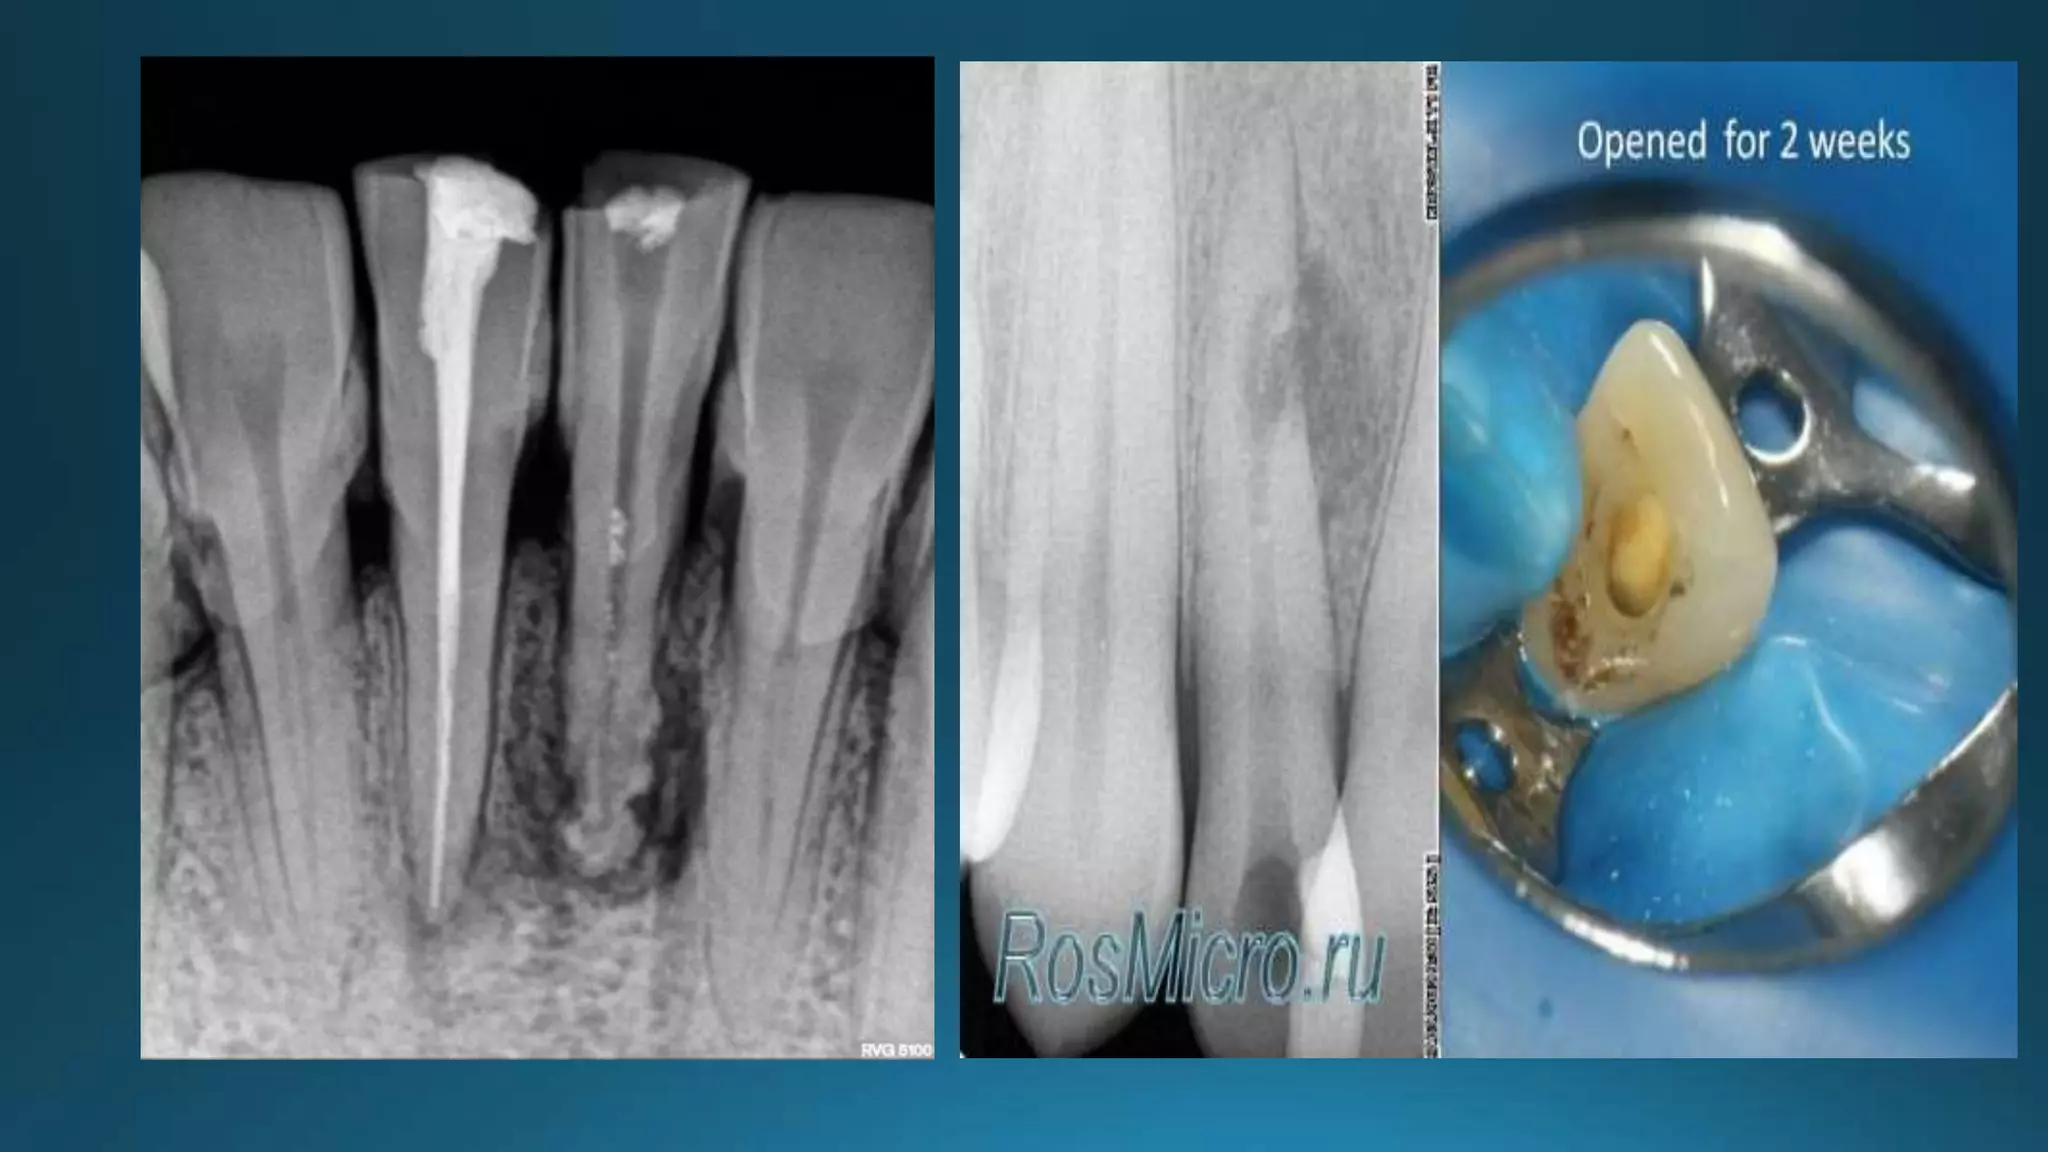

Areas of resorption

RESORBED APEX

Treatment of open apex with no vital pulp